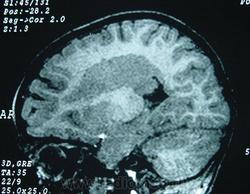

Гетеротопии. Перивентрикулярная гетеротопия. Субэпендимальная нодулярная (узелковая) гетеротопия.

Наиболее частым вариантом миграционных нарушений является гетеротопия - скопление нейронов, остановившихся в различных аномальных местах на пути следования к коре головного мозга. Такая остановка происходит не позже 5-го месяца внутриутробного развития. Изолированный участок узловатой массы называется «гетеротопион». В настоящее время описаны следующие варианты гетеротопии:

- субэпендимальная нодулярная (узелковая) гетеротопия;

Перивентрикулярная субэпендимальная гетеротопия